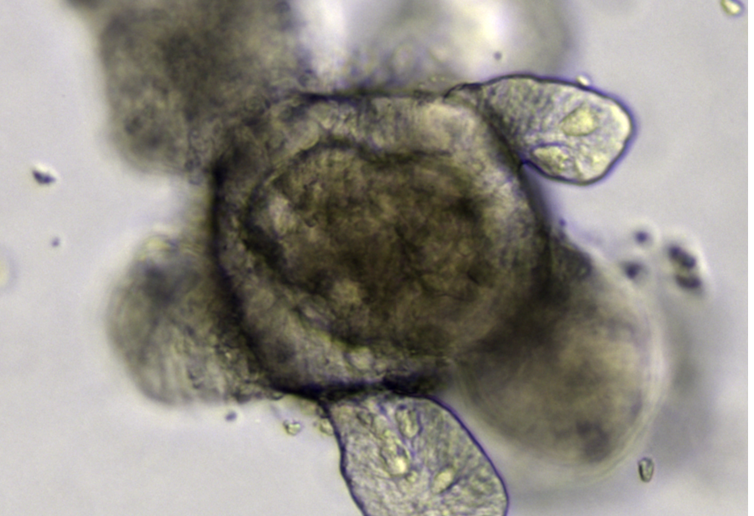

Grâce à une collaboration avec l’équipe de Jeff Beekman, aux Pays-Bas, nous avons pu tester la DAP sur des organoïdes intestinaux.

Ces « mini-organes » sont des assemblages de cellules dont l’organisation rappelle celle de l’organe dont ils sont issus (dans notre cas, l’intestin, car les cellules utilisées dérivaient de cellules issues d’une biopsie rectale). L’intérêt est d’obtenir une architecture et des fonctionnalités proches de celle de l’organe originel.

Organoïde intestinal cultivé à partir de cellules souches Lgr5+ Meritxell Huch, CC BY

L’ajout de DAP dans le milieu de culture de ces organoïdes a permis, là encore, de restaurer la fonction de la protéine CFTR. Et ce, avec une efficacité comparable à celle d’un médicament déjà utilisé pour traiter des patients atteints de formes de mucoviscidose dues à un autre type de mutation que des mutations non-sens.

Ce résultat corrobore l’hypothèse que la DAP pourrait constituer un candidat médicament pertinent pour le traitement des mucoviscidoses liées à des mutations non-sens.